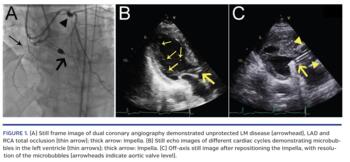

A 65-year-old male with triple-vessel coronary disease, recent repaired abdominal aortic aneurysm, and chronic kidney disease deemed high risk for surgery was referred for coronary revascularization. Given his unprotected left main anatomy, we proceeded with Impella-supported revascularization of the left main, left anterior descending artery, and right coronary artery (Figure 1A). Following a long but successful intervention, we decided to continue with Impella support to maintain renal perfusion after the procedure. After non-traumatic Foley catheter insertion for urine output monitoring, we observed frank hematuria. Labs exhibited hemolysis. Echocardiogram demonstrated bubbles in the left ventricle (Figure 1B and Video 1). Repositioning of the device was undertaken with echocardiographic guidance and resulted in optimal flow parameters and significant decrease in the amount of bubbles in the left ventricle (Figure 1C and Video 2). Twelve hours later, hemolysis was still occurring, as evidenced by a drop in hemoglobin, increase in lactase dehydrogenase, and decrease in haptoglobin. Thus, the decision was made to remove the Impella device. The hematuria resolved by the next day and the hemoglobin remained stable. The patient was discharged from the hospital.